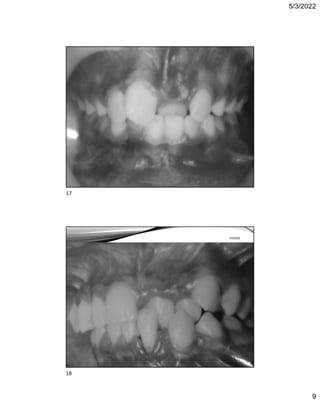

Figure 6.16 Traumatic overbites causing palatal (left panels) and labial (right panels) gingival trauma.